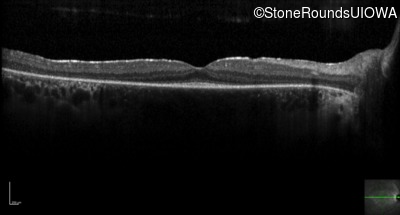

Optical Coherence Tomography - Left -

20/20

Exemplar / OCT Stack